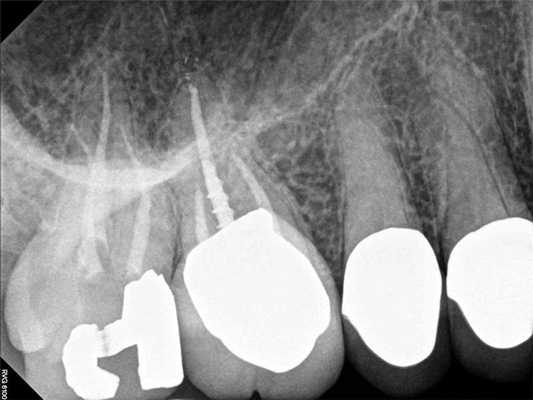

75-летний пациент мужского пола обратился за стоматологической помощью с основной жалобой на сильную, плохо локализованную боль с правой стороны челюсти и лица, которая началась еще неделю назад. Он описал боль как пульсирующую и указал, что она распространяется от средней линии лица до правого уха как в проекции верхней, так и нижней челюсти. Пациент также сообщил, что воздействие тепла усугубило симптомы, и он может облегчить боль только держа во рту холодную воду. Небольшое облегчение было отмечено при пероральном приеме комбинации 600 мг ибупрофена плюс 500 мг ацетаминофена. Хотя такая основная жалоба пациента, как правило, связана с патологией дегенеративного пульпита, но в ходе клинического осмотра и рентгенологической диагностики не было обнаружено никаких примечательных изменений. Зубы с правой стороны верхней и нижней челюсти не демонстрировали признаков чрезмерной чувствительности на тепловые раздражители, перкуссию и пальпацию. Также у пациента не было идентифицировано признаков припухлости или формирования свищевого хода, подвижность зубов была в границах физиологического диапазона, а глубина пародонтального зондирования не превышала физиологической границы. На первичных рентгенограммах зубов 30 и 31 была верифицирована нормальная ширина пространства пародонтальной связки и ретенция 32 зуба. В структуре 32 зуба визуализировалась небольшая область просветления, находящаяся близко к дистальной поверхности корня 31 зуба (фото 2-3).

Фото 2. Клинический случай 1. Рентгенограмма области дистального правого квадранта верхней челюсти без выраженных признаков изменений.

Фото 3. Клинический случай 1. Рентгенограмма области дистального правого квадранта нижней челюсти без выраженных признаков изменений. Наличие ретинированного моляра.

Чтобы купировать выраженные болевые ощущения пациента была проведена блокада нижнего альвеолярного нерва посредством 3,4 мл 0,5% раствора бупивакаина с концентрацией эпинефрина 1:200000. Через 5 минут после анестезии пациент сообщил о полном разрешении боли. Учитывая факт купирования болевых симптомов после выполнения анестезии, было предположено, что этиология таковых является одонтогенной. В ходе выполнения повторной рентгенографии была визуализирован участок внутрикоронковой резорбции непрорезавшегося 32 зуба. Пациент был направлен к челюстно-лицевому хирургу с целью удаления проблемного зуба. После экстракции больной сообщил, что все симптомы боли разрешились. После выполнения экстракции был подтверждён диагноз внутрикоронковой резорбции 32 зуба.

Фото 4. Клинический случай 1. После выполнения анестезиологической блокады было проведенного повторное рентгенологическое обследование, которое позволило обнаружить внутрикорональную резорбцию в структуре ретинированного моляра, которая спровоцировала развитие симптомов необратимого пульпита.